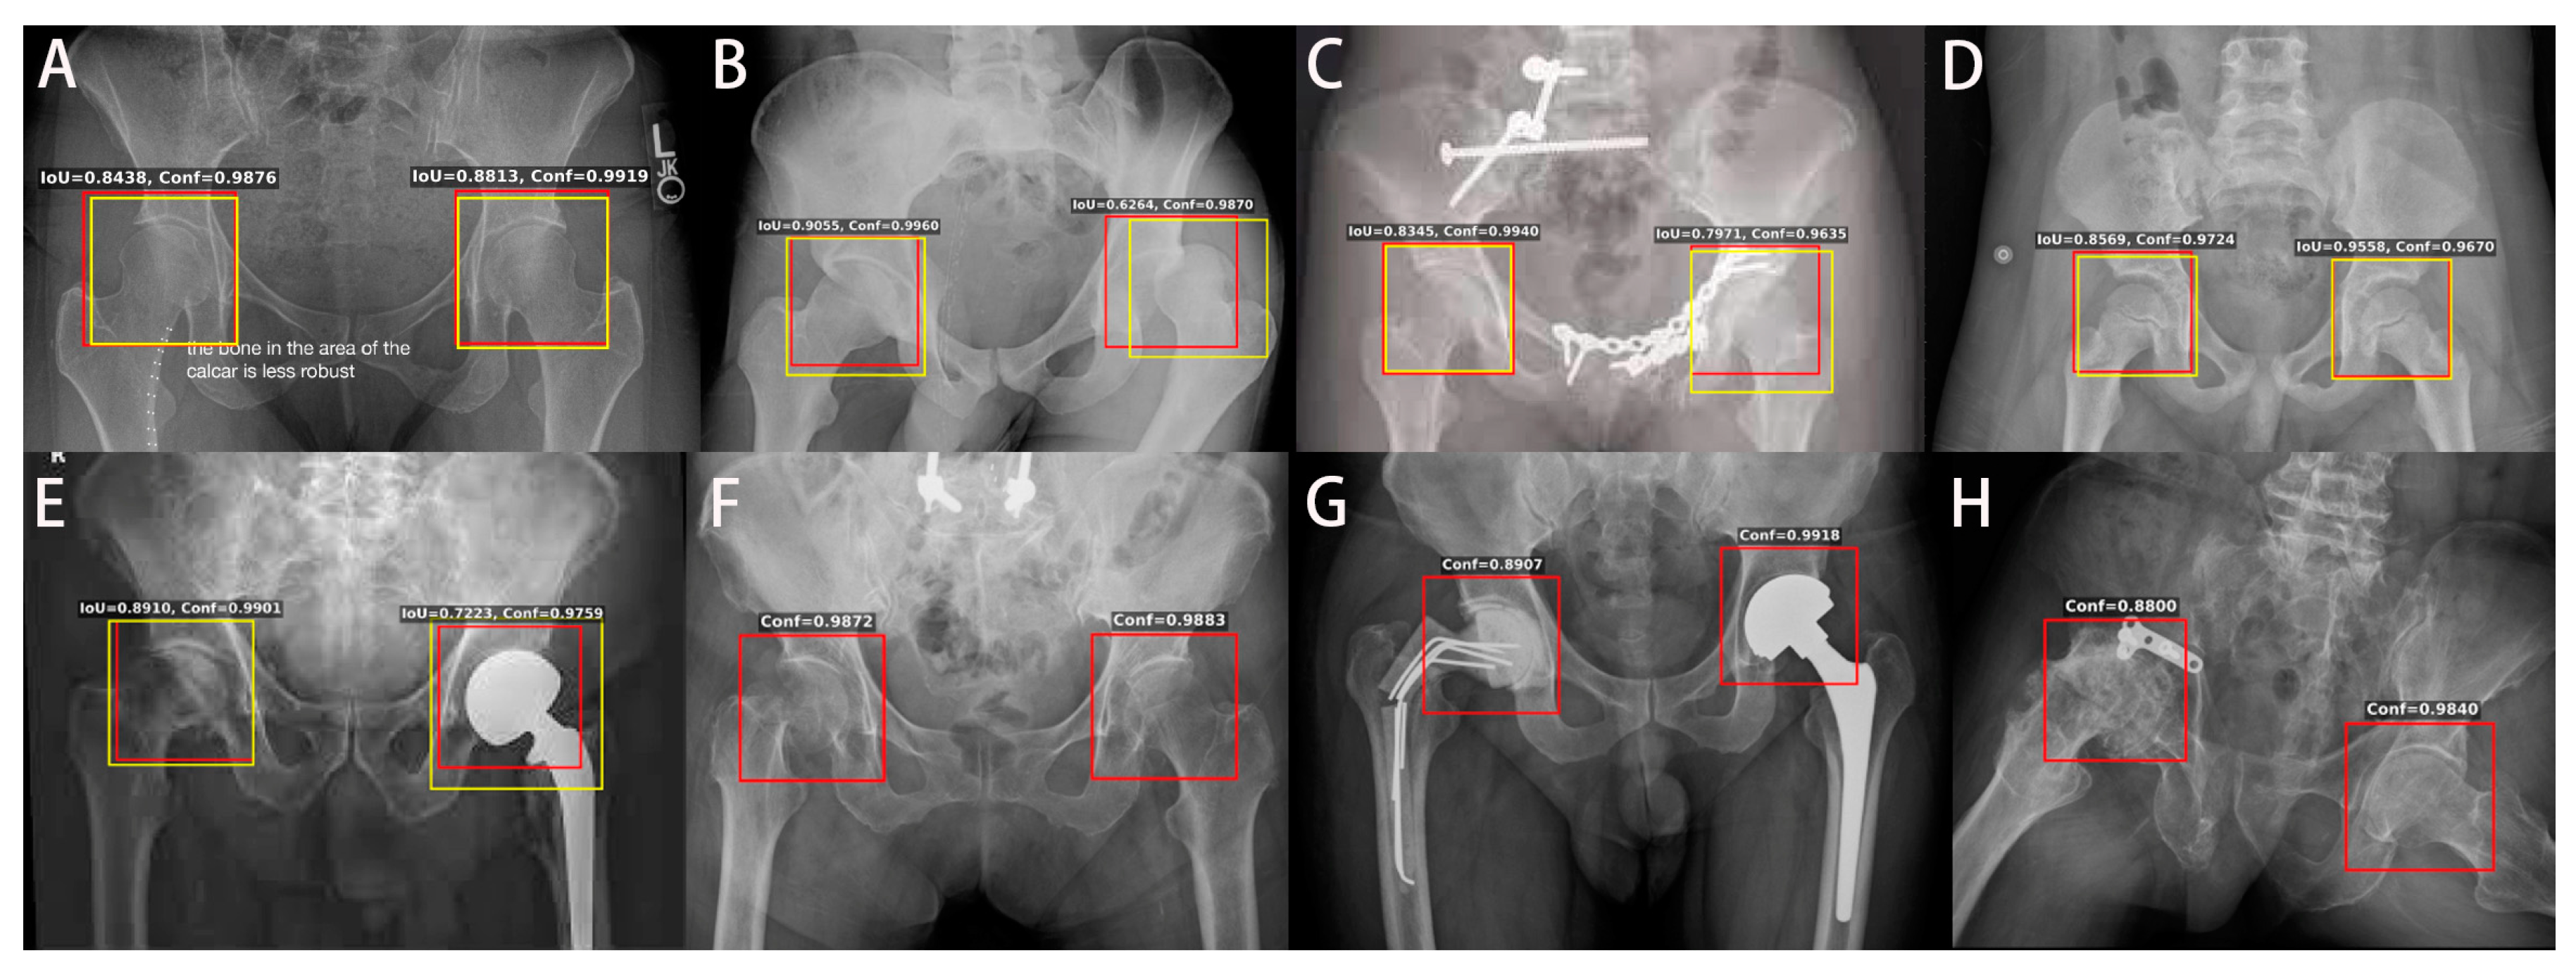

3.2. Model Performance and Visualization

| All: CGOA & OAIH & GIS | 7399 | 14,798 | 0.9176 | 0.9688 | 0.3861 | 2 | 0.9999 |

| Train: 90% CGOA & OAIH | 6568 | 13,136 | 0.9260 | 0.9698 | 0.5955 | 0 | 1 |

| Valid: 10% CGOA & OAIH | 730 | 1460 | 0.8571 | 0.9582 | 0.5907 | 0 | 1 |

| Test: GIS | 101 | 202 | 0.8115 | 0.9812 | 0.3861 | 2 | 0.9901 |